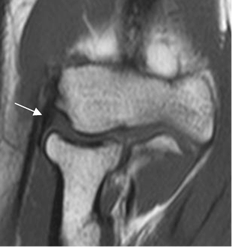

Los ligamentos son engrosamientos fibrosos de la cápsula y se valoración requiere de imágenes coronales oblicuas y axiales de RM. (1). (Fig 17, 18, 19, 20 y 21). La prueba de elección para su valoración, es la ArtroRM guiada con fluoroscopia. (9).

Fig 17. Ligamento colateral medial normal.

Banda anterior, en secuencia T1 coronal.

Fig 18. Ligamento colateral medial normal.

A: RM coronal y B: RM axial en T1. Banda posterior normal.